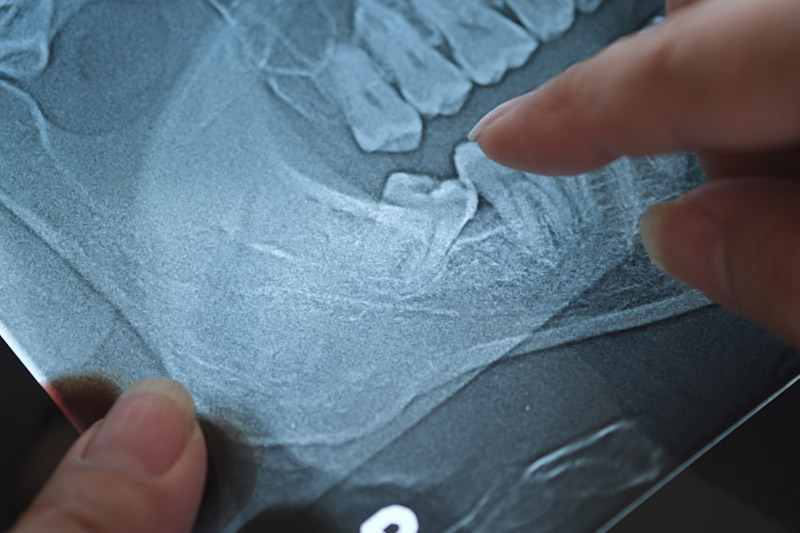

If a tooth is impacted (below the gumline), our dentist will numb the area and then cut away gum and bone tissue that cover the tooth in order to remove it. Sometimes, a hard-to-pull tooth has to be removed in pieces; but again, you should only feel some pressure, no pain.